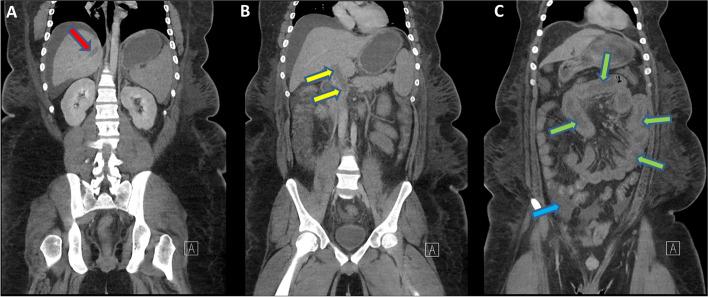

An unvaccinated young adult male with steroid-dependent nephrotic syndrome (SDNS) who was in a complete nephrotic remission relapsed following contracting SARS-CoV-2 infection and developed abdominal pain and diarrhea. Abdominal US revealed portal vein thrombosis. The patient was anticoagulated, yet the SVT rapidly propagated to involve the spleno-mesenteric, intrahepatic and the right hepatic veins. In spite of mechanical thrombectomy, thrombolytics and anticoagulation, he developed mesenteric ischemia which progressed to gangrene leading to bowel resection and a complicated hospital course.

一名未接种疫苗的年轻成年男性患有激素依赖性肾病综合征(SDNS),在感染 SARS-CoV-2 后完全缓解的肾病综合征复发,并出现腹痛和腹泻。腹部超声显示门静脉血栓形成。患者接受了抗凝治疗,但 SVT 迅速传播累及脾-肠系膜、肝内和右肝静脉。尽管进行了机械血栓切除术、溶栓和抗凝治疗,但他仍发生肠系膜缺血,进而发展为坏疽,导致肠切除术和复杂的住院过程。